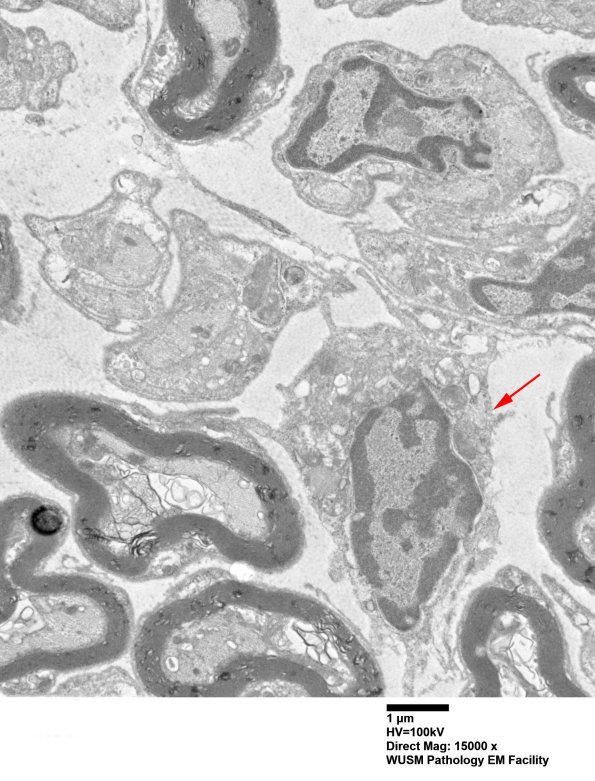

There are numerous relatively undifferentiated cells (arrow) which have the pseudopods of macrophages without autophagic content. (electron micrograph)